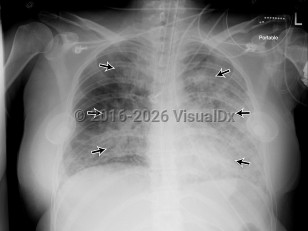

Acute respiratory distress syndrome

Clinically, ARDS is characterized by decreased compliance in the lungs ("stiff lungs"). On a microscopic level, it involves alveolar edema due to increased permeability from membrane destruction ("leaky capillaries") as well as neutrophil infiltration, which can lead to activation of a localized inflammatory response. Once the alveoli are damaged, they will start to collapse, leading to atelectasis derecruitment of the lung. Although mechanical ventilation is the mainstay of treatment, it can be challenging and must be done carefully and within specific parameters, as repetitive re-expansion and collapse of the alveoli can lead to mechanical injury known as atelectrauma and the elevated mean airway pressures or excess tidal volumes in the setting of decreased lung compliance result in alveolar barotrauma / volutrauma.

The Berlin Definition of ARDS was published in 2012, identifying specific criteria for diagnosis.